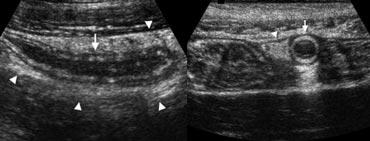

Hình 3. Nữ giới 19 tuổi bị viêm ruột thừa. Siêu âm theo mặt phẳng dọc và ngang cho thấy ruột thừa phóng to (mũi tên) được bao quanh bởi mô mỡ viêm tăng âm (đầu mũi tên).

Một dấu hiệu hỗ trợ khác cho viêm ruột thừa là tăng sinh mạch máu của thành ruột thừa trên siêu âm Doppler màu [1] (Hình 3b).